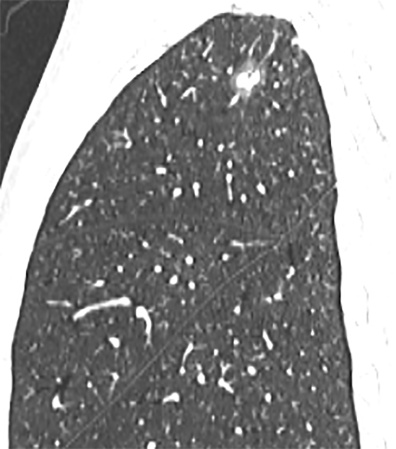

单因素分析显示,CEA、肿瘤最大径、实性成分最大径、CTR、cT分期、边界、分叶征、毛刺征与STAS表达状态显著相关(P均<0.05),将上述特征纳入多因素logistic回归分析,结果表明CEA、肿瘤最大径、cT分期以及毛刺征是STAS阳性的独立预测因素(P均>0.05) (表2)。图1展示了1例STAS阳性患者的CT图像。

(a) (b) (c)

Figure 1. A 57-year-old male patient with STAS-positive lung adenocarcinoma. Axial (a), coronal (b), and sagittal (c) CT images show a part-solid nodule in the right upper lobe, with a well-defined boundary,containing a solid component and peripheral lobulation

1. STAS阳性肺腺癌患者,男,57岁。横轴位(a)、冠状位(b)、及矢状位(c) CT图像示右肺上叶部分实性结节,边界清晰,内可见实性成分,周边可见分叶征